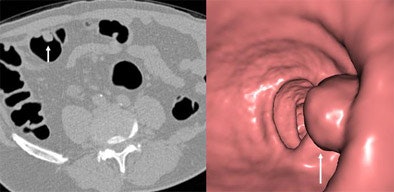

![]() |

| A 13-mm pedunculated polyp is detected in a male patient in his 50s referred for virtual colonoscopy screening, as seen in both 2D axial image (left) and 3D endoluminal view (right). Images courtesy of Dr. Michael Macari. |